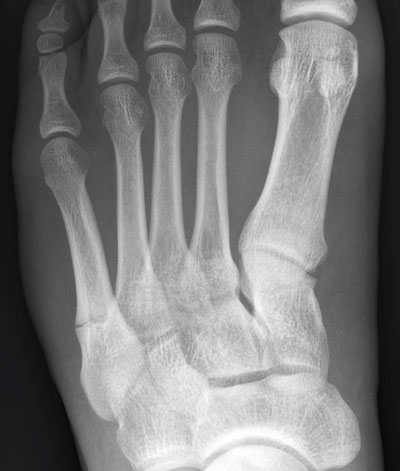

Belastningsutlösta smärtor och ömhet i benet omkring frakturen är typiskt vid stressfraktur [20]. Smärtorna minskar med vila. I de allra flesta fall kan slätröntgen ge diagnosen [21]. Efter några veckor bildas en kallusreaktion, som man kan se som en benpålagring både periostalt och endostealt. Ibland kan man se en frakturlinje som löper vinkelrätt mot benets längsaxel (Figur 5). Sprickan kan dock vara för tunn för att synas.

Figur 5. Stressfraktur med tvärgående frakturlinje och kallusreaktion i tibia (överst) och femte metatarsalbenet (ovan).